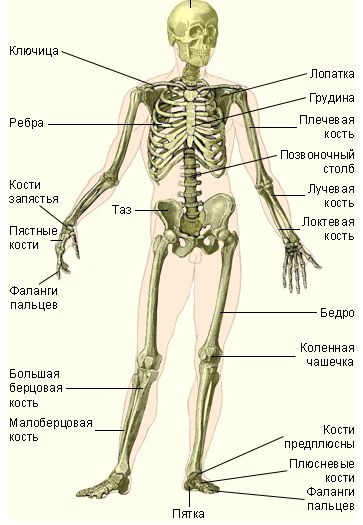

Скелетная или опорно-двигательная (кости, хрящи, связки) система

Основой нашего передвижения является скелет, который является главной опорой для всего остального. К скелету крепятся мышцы, присоединяются они с помощью связок (мышцы умеют растягиваться, связки нет) благодаря этому кость может быть поднята или отодвинута.

Разбирая свойства скелетной системы можно отметить, что главное в ней – это опора для тела и защита внутренних органов. Опорный скелет человека включает в себя 206 костей. Главная ось представляет собой 80 костей, добавочный скелет состоит из 126.

Кости скелетной системы человека

Основные кости скелетной системы человека :

— Череп;

— Нижняя челюсть;

— Ключица;

— Лопатка;

— Грудина;

— Ребро;

— Плечевая;

— Позвоночный столб;

— Локтевая;

— Лучевая;

— Кости пясти;

— Фаланги пальцев кисти;

— Таз;

— Крестец;

— Бедренная;

— Коленная чашечка;

— Большая берцовая;

— Малая берцовая;

— Кости предплюсны;

— Кости плюсны;

— Фаланги пальцев стопы.

Для того, чтобы понять как правильно ликвидировать переломы, а также определить, какие именно кости подвержены серьезным воздействиям, необходимо ознакомиться с костной системой человека. Человеческий скелет представлен на рисунке ниже:

Рис. 2.1. Скелет человека

На рисунке виден скелет человека, а также названия некоторых костей. Как можно увидеть, скелет состоит из следующих частей: Череп, ключица, лопатка, грудина, плечевая кость, ребра, позвоночный столб, лучевая кость, локтевая кость, таз, кости запястья, пястные кости, фаланги пальцев, бедро, коленная чашечка, большая берцовая кость, малоберцовая кость, кости предплюсны, плюсневые кости, пятка. Все это в совокупности составляет человеческий скелет. Если рассматривать скелет по отдельности, то можно выделить несколько частей. Одной из таких частей является скелет верхней части: